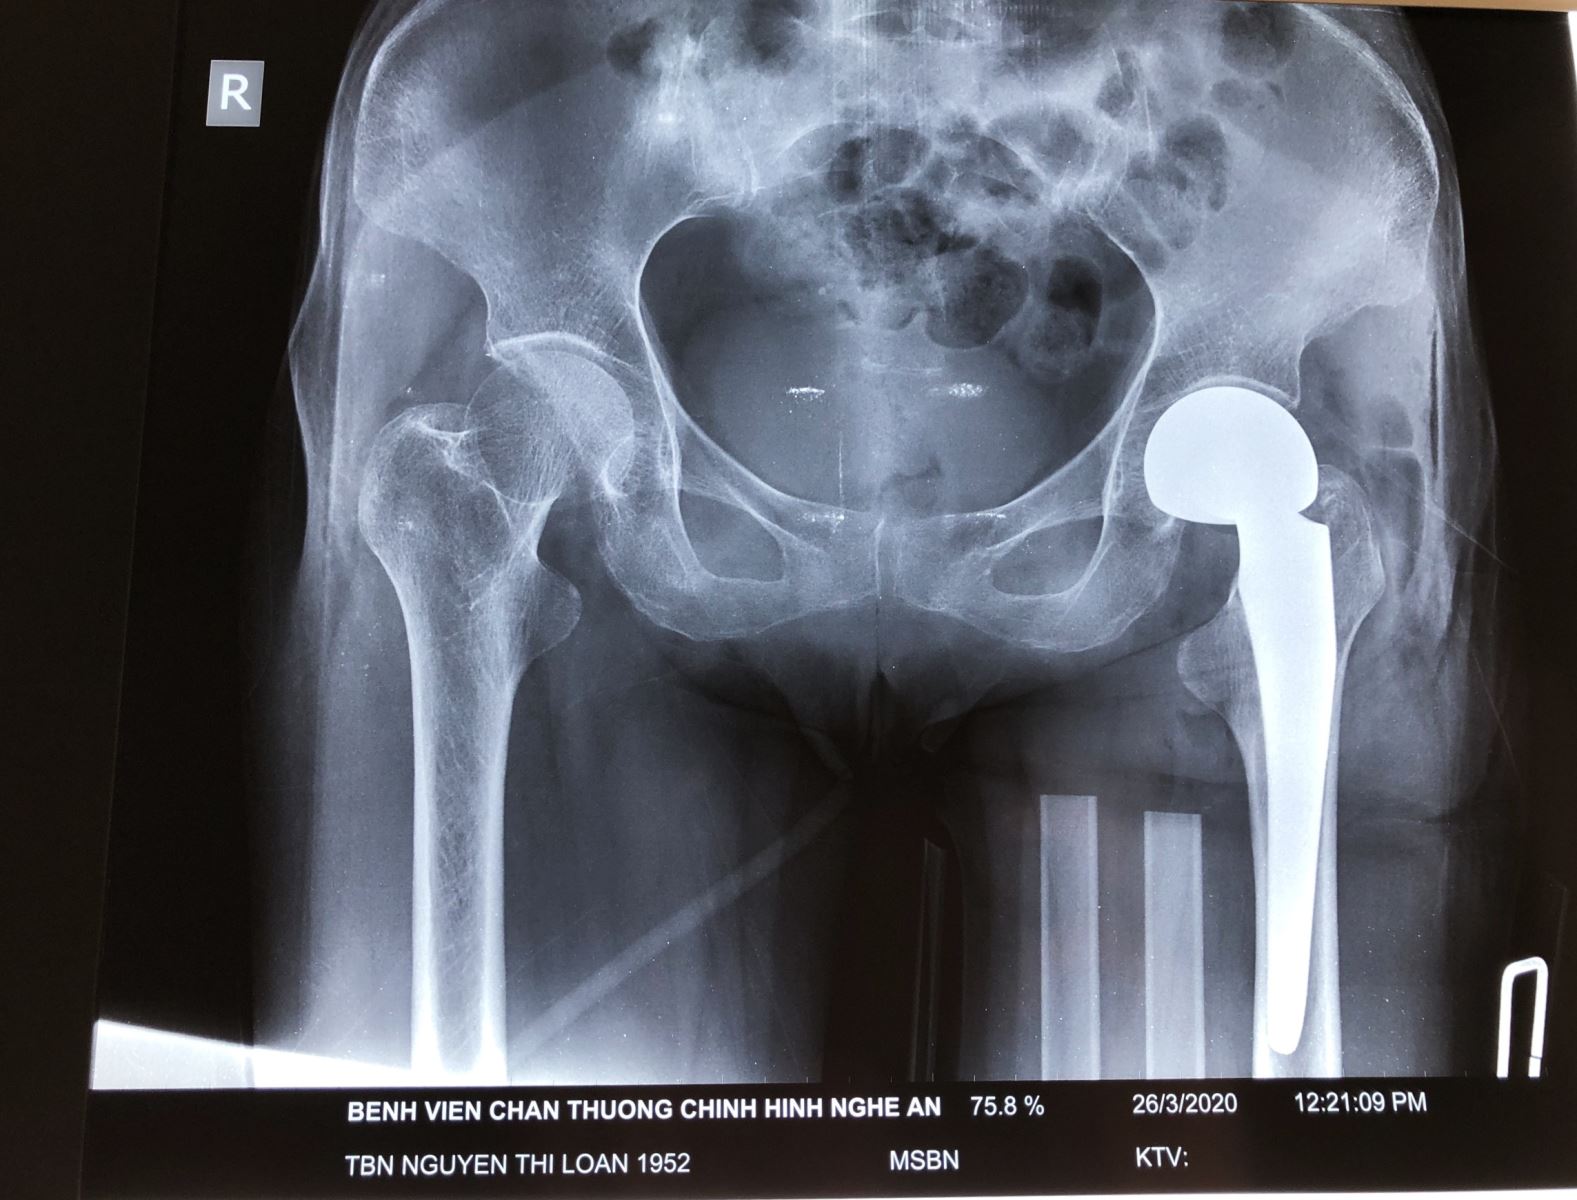

Bệnh nhân Nguyễn Thị Loan, 68 tuổi, ở TP.Vinh – Nghệ An có tiền sử  parkinson, đã điều trị 6 năm nay. Đợt này bệnh nhân trượt chân ngã gây đau biến dạng, hạn chế vận động đùi háng trái. Vào Bệnh viện Chấn thương Chỉnh hình Nghệ An, bệnh nhân được chẩn đoán gãy cổ xương đùi trái.

Sau khi tiến hành hội chẩn, bệnh nhân được chỉ định phẫu thuật thay khớp háng bán phần. Ca phẫu thuật được tiến hành thành công bởi kíp mổ của ThS, Bác sĩ Nguyễn Hoài Nam – Giám đốc Bệnh viện và các cộng sự.

Hình ảnh phim chụp Xquang của bệnh nhân trước và sau phẫu thuật thay khớp háng